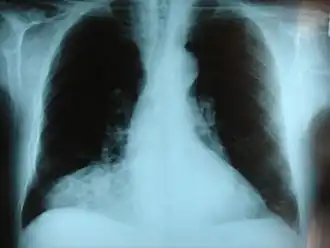

- une hernie diaphragmatique,

- une hernie hiatale,